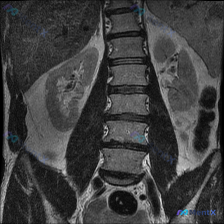

整理到一份腹部MRI冠状位T2WI的影像资料,有几个点觉得值得拿出来讨论: 1. 影像核心表现: - 右肾后方及右侧腹膜后可见大片均匀T2高信号区,边界较清,有占位效应,把右肾向内上方推挤了 - 左肾皮髓质分界尚可,肾盂肾盏是生理性T2高信号,输尿管走行区没看到明显串珠状扩张 - 图像里肝脏边缘、部...